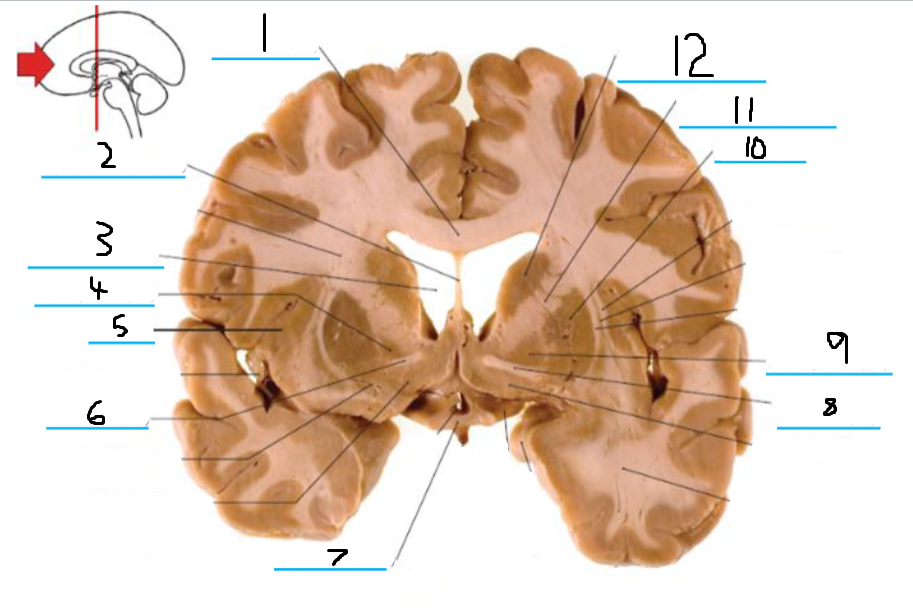

#3 and #16 are the:

Thalamus

#4 is the:

Hypothalamus

#5 and #9 is the:

Hippocampus

#6 is the:

Crus Cerebri

#7 is the:

Basilar Pons

#8 is the:

Mammillary Body

#10 is the:

Caudate

#11 is the:

Third Ventricle

#12 is the:

Globus Pallidus

#13 is the:

Insula

#14 is the

Putamen

#15 is the:

Internal Capsule

#17 is the:

#18 is the:

Lateral Ventricle

#19 is the:

Corpus Callosum